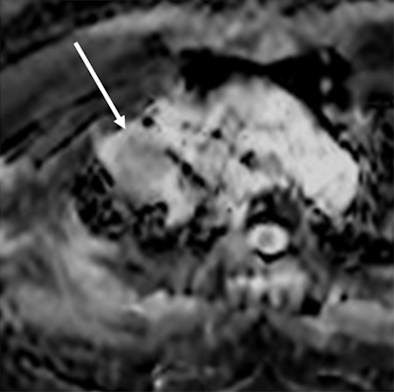

| MR images of a 75-year-old woman with lung cancer who achieved a partial response after two rounds of chemotherapy. ADC maps obtained before (above) and after (below) one course of treatment indicate that the ADC value of the lesion (arrow) increased from 0.99 to 1.48 x 10-3 mm2/sec after therapy. Images courtesy of Radiology. |

The median progression-free survival for the group with good ADC increase was 12.1 months, compared with 6.7 months for the group with poor ADC increase. In addition, the median overall survival period was 22.4 for the good ADC increase group, compared with 12.3 months for the poor ADC increase group.